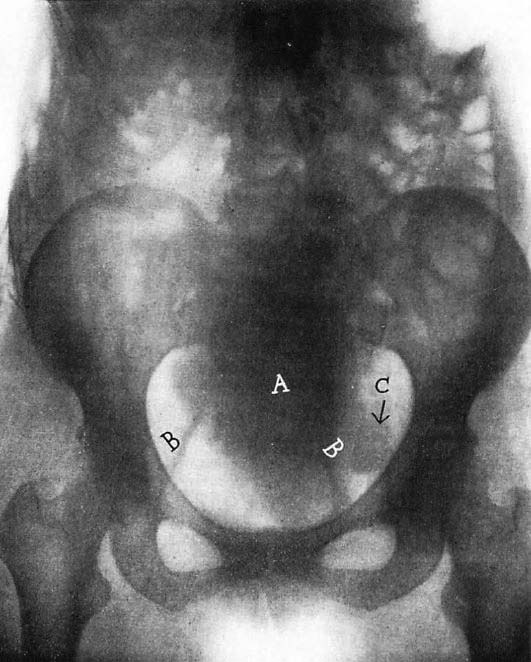

図3. 羊水胎児造影.油性造影剤が胎表に付着して輪郭が明瞭に描出される[17].

胎嚢内に造影剤を注入する羊水造影は,侵襲的な方法であるが当時としては最も直接的に胎児を描出できる方法であった.1930年,Menees[→原著論文]は初めてヨウ化ストロンチウムを造影剤としてこれに成功し,胎児の状態を診断し,前置胎盤の診断も可能であることを示した.論文では無害としているが,その後早産の原因となることがわかり,毒性の低い有機ヨード造影剤に変えられた.1972年に,オランダのWiesehaan[17]が,水溶性造影剤と油性造影剤を併用する方法を開発した(図3).水溶性造影剤で羊水腔を造影すると同時に,油性造影剤がアルカリ性の胎脂を鹸化して胎表に付着することにより,胎児の輪郭を描出する胎児造影(fetography)が可能となり,その後標準的方法となった.この羊水胎児造影は1970年代まで最も確実な胎児画像診断法として用いられたが,超音波検査の発展とともにその役割を終えた.

図5. 羊水造影.骨盤内に児頭,右側に脊椎がみえる.左上腹部の索状透亮像は臍帯.

【要旨・解説】羊水造影の初報である.前腹壁を穿刺してヨウ化ストロンチウムを7.5~15cc注入した.21例に行ない,有害作用はなかったとしている.妊娠6ヵ月の1例は,検査の30時間後に分娩し,胎盤部分剥離があり注射針が胎盤を貫通していたと記載しながら,臍帯に拍動があったことから有害作用は否定的,とされている点は理解に苦しむところである. 後前撮影,側面撮影を行い,良い側面像(プロフィール像)が得られれば胎盤の位置を知ることができる(図5).臀部の良い画像が得られれば,陰嚢の有無によって性別も判定できる.

羊水造影は侵襲が大きいものの,超音波検査やMRIがなかった当時,胎児の状態を直接確認することができる貴重な検査法として認識され,臨床に広く供された.特に1972年にWiesehaan[17]が油性造影剤をして胎表を造影する羊水胎児造影を開発して標準的な方法として確立した.